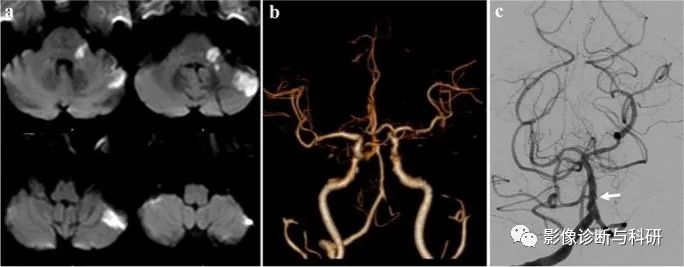

弥散加权图像显示左侧脑桥臂和左侧小脑上外侧出现急性梗塞(a)。计算机断层扫描血管造影显示左侧椎动脉狭窄和闭塞,并且双侧小脑前下动脉(AICA)缺失(b)。DSA显示左近端 AICA 闭塞(c)